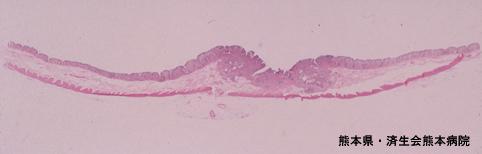

Posted by: Kumamoto Pref., 济生会熊本病院 (Dr. 吉田)

疾病(病理主体)的分类恶性上皮性肿瘤/腺癌

部位(按器官分)大肠/横结肠

检查方法病理切片(微观)

肿瘤的肉眼分类0型(表在型)/IIa型(IIa+IIc)

肿瘤最大直径20~24

肿瘤的深度sm